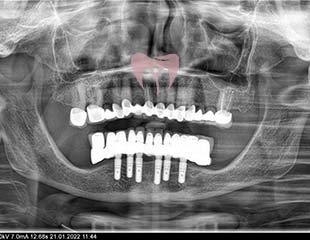

For treating missing teeth in the mouth we can use dental implants. The best way of implants; restore your lost aesthetics and function.

- Life Time Guarantee for Dental Implants